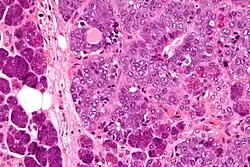

| Micrograph of an epithelial-myoepithelial carcinoma (right of image). The epithelial component has a tubular morphology and is evident only focally (upper left of image). Benign serous glands (parotid salivary gland) are also seen (left of image). H&E stain. | |

This tumour is characterised by biphasic tubular structures composed of inner ductal and outer clear myoepithelial cells.

Its appearance is very similar to adenomyoepithelioma of the breast, which may be the same tumour at a different anatomical site.[3]

The histologic differential diagnosis includes adenoid cystic carcinoma and pleomorphic adenoma.